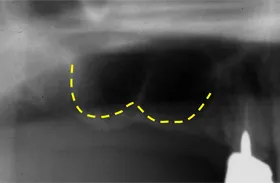

■治療前

向かって左の下の奥歯が、長期間失ったまま放置されていました。その為、向かって左奥の2本の歯が、前に倒れるように傾いてしまっていました。

まず、この傾きを治しました。治療期間は4ヶ月です。

■治療中

■治療中レントゲン写真

その後、歯を失った場所には、人工の歯根であるインプラントを埋めて、白い歯をかぶせました。

■治療後レントゲン写真

このようにして、従来なら前と後ろの歯を削って治していくブリッジにせずに、治すことができました。

| 主訴 | 右下の奥歯をずいぶん前に抜きそのままにしていたら、奥歯が倒れてきた |

| 治療方法 | 部分矯正治療+インプラント治療 |

| 治療期間 | 約10か月 |

| 通院回数等 | 12回位 |

| 費用 | 約80万円 |

| リスク・副作用 | インプラント術後の腫れ・痛み |